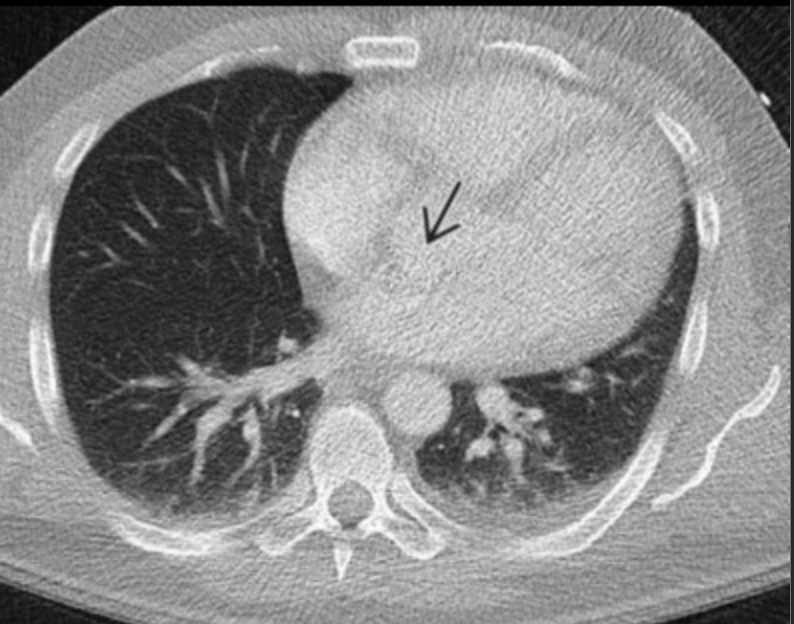

Ring artifact

• Looks like a ring that should not be there

• Only seen in 3rd gen scanners

• Caused by defective detector elements

• Can only be fixed by fixing the scanner

• Image from radprimer